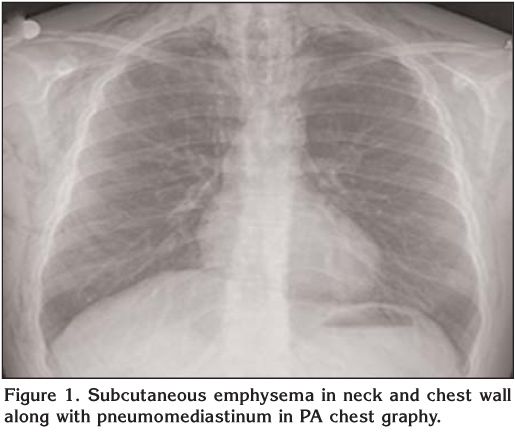

A 17 year-old male patient applied to emergency room with chest pain, mild dyspnea and rising swelling in neck following a cough two days ago. Chest X-ray and routine biochemical parameters were normal and he was recommended to apply to pulmonology outpatient clinic along with certain medical prescriptions. He reapplied to emergency room upon progressing complaints two days later. In the initial evaluation, the Glasgow Coma Scale was 15 while oxygen saturation 95%, arterial blood pressure 115/85 mmHg, heart rate 95/minute and body temperature 37.5?C. Respiratory examination revealed no abnormal finding, however, subcutaneous crepitations extending scapula were detected around neck region in palpation. No other systemic abnormalities were observed. Electrocardiography was normal. Those noted in PA-chest X-ray were subcutaneous air in bilateral neck and chest wall, together with pneumomediastinum (Figure 1). Pneumomediastinum, minimal pneumothorax and extensive air collection within soft tissues in whole chest wall and neck were observed in computed tomography taken for verification of pathological findings observed in chest X-ray (Figure 2). Having no history of smoking along with individual or familial disorder, he was diagnosed with Primary spontaneous pneumothorax (PSP). Despite extensive pneumomediastinum and subcutaneous emphysema, he had minimal pneumothorax and was admitted to inpatient clinic of pulmonology. Following high-frequency oxygen therapy (10 L/minute) in pulmonology clinic, his complaints and radiologic findings improved and he was discharged. Because this is an uncommon case, it has been thought to be presented here.

Figure 1